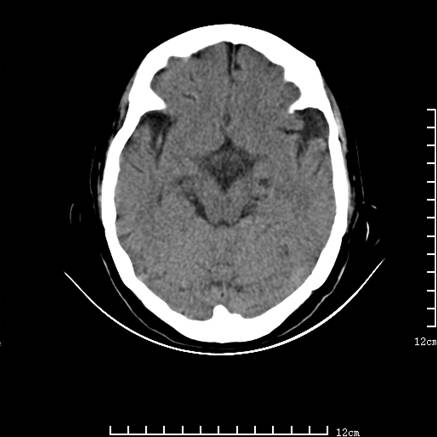

标题: V0514:女,72岁,偶有头晕,自诉记忆力减退,来诊。 [打印本页]

标题: V0514:女,72岁,偶有头晕,自诉记忆力减退,来诊。

是拉特可囊肿(rathke cyst)吗?

考虑垂体瘤可能性大

1、考虑垂体腺瘤。

垂体腺瘤可能性大!另:轻度脑萎缩!

考虑垂体腺瘤可能性大。脑萎缩。

考虑垂体腺瘤可能性大。脑萎缩。  建议mri 检查

垂体瘤,建议mri

垂体腺瘤